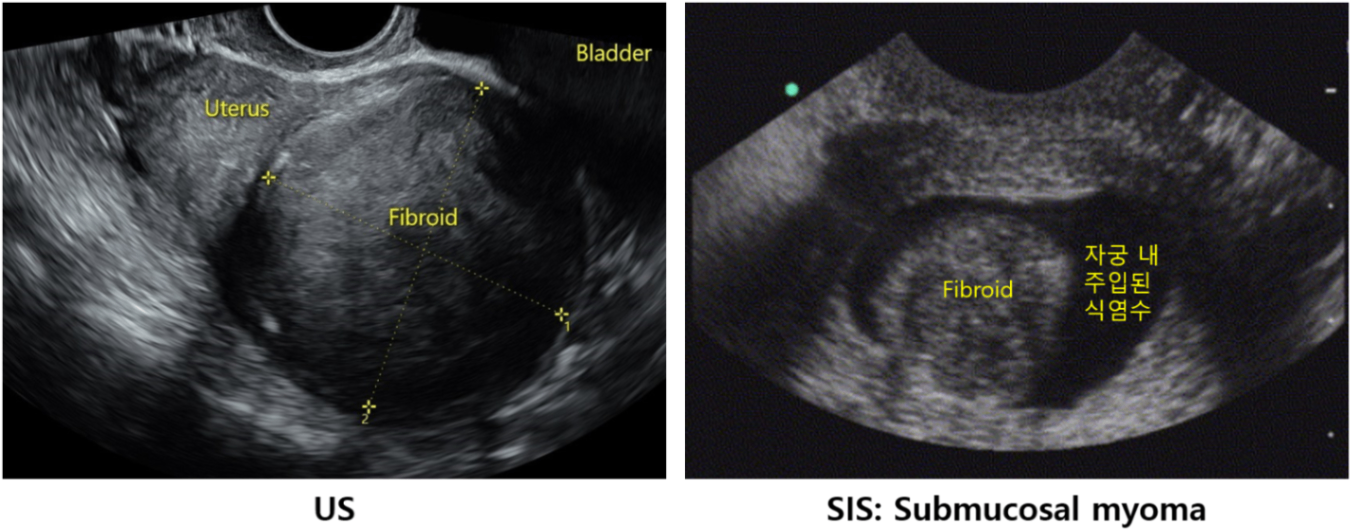

(1) US: 경계가 명확, 저에코성, 대칭성, heterogeneous한 mass (↔ 자궁샘근육증은 경계가 불명확함)

(2) 식염수 주입 US(saline infusion sonography, SIS): Submucosal 근종에 대한 효과적 진단 가능